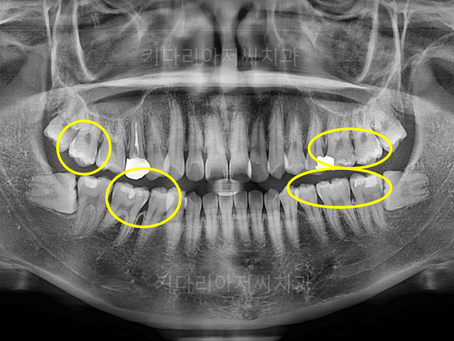

연산동사랑니치과 교정 종료 후, 충치치료 및 사랑니 발치를 한 치료사례